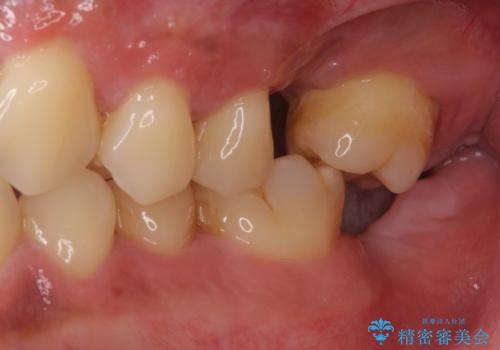

- ソーシャルメディアでのゲームに夢中になっている最中に車と接触し、前歯の抜歯を余儀なくされた患者様です。

初診時では前歯が保存できる可能性も模索しましたが、損傷が激しく3歯を抜去することとなりました。

保存となった隣在歯も神経が失活していており、補綴治療が必要であったので、オールセラミッククラウンにて補綴治療することとしました。

奥歯には元々欠損があり、欠損に伴う咬合不正も認められたため、部分矯正を行った上でインプラント補綴治療も行うこととしました。